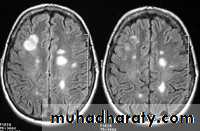

- the most characteristic appearance is that of peri ventricular nodular Hyper intense lesions on T2 weighted images.

-the plaques are also well seen at the gray- white matter interfaces.

-some lesion may show a central area of greater signal intensity , resembling a target.

SAGITAL FLUID ATTENUATION INVERSION RECOVERY SEQUENCE: OVOID PLAQUES ( HIGH SIGNAL INTENSITY) , WHICH ARE PERPENDICULAR TO LATERAL VENTRICLE.